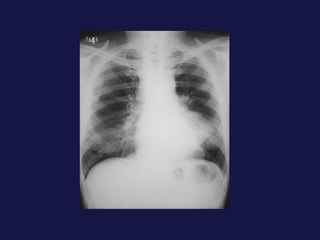

Carcinoma bronquioloalveolar  (1.5-6,5%) Subtipo de adenocarcinoma. Empieza como nódulo periférico, espiculado, hasta parecer una masa considerable, condensación alveolar o infiltrados múltiples 50% con cola pleural. Es FREC. el broncograma aéreo, puede presentar cavitación.